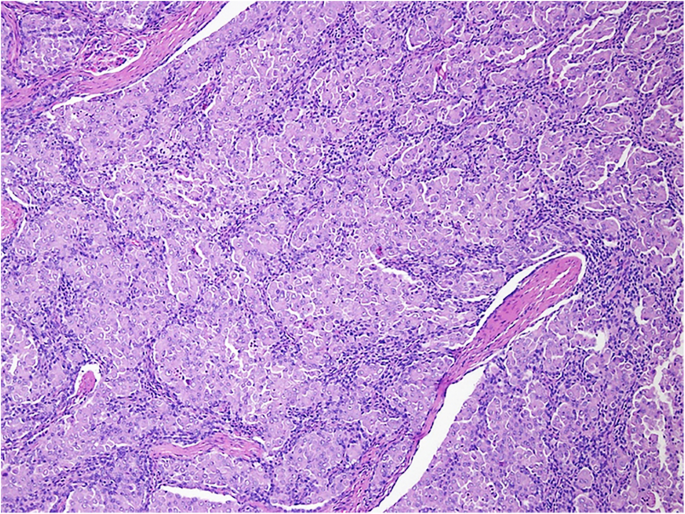

Микроскопический взгляд на мишитарный туберкулез легкого: фотодокументация